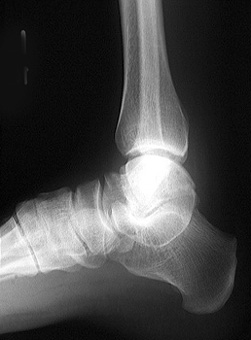

Look at the radiographs below. The talo-calcaneal coalition is best seen on the oblique view. Can you see it? Look for disruptions of the subtalar joint.

Lateral view